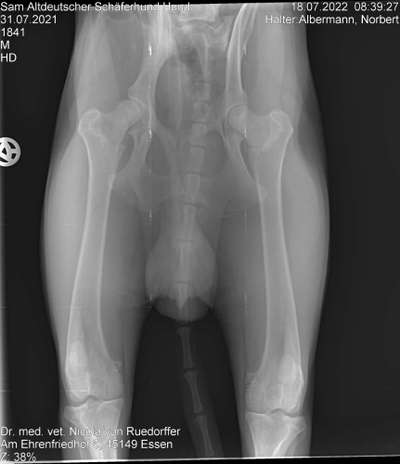

Hallo, bei Sam wurde HD diagnostiziert. Was kann ich tun?